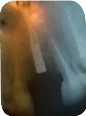

レントゲン写真を観察

レントゲンを撮ってみると、ZIMMER BIOMETのインプラントか、ノーベル(インプラントメーカー)のインプラントに近い形をしていますが、わずかに違います。